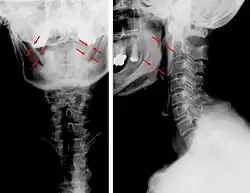

| Anteroposterior and lateral radiographs of cervical spine showing ossification of the stylohyoid ligament on both sides | |

Eagle syndrome (also termed stylohyoid syndrome,[1] styloid syndrome,[2] stylalgia,[3] styloid-stylohyoid syndrome,[2] or styloid–carotid artery syndrome)[4] is an uncommon condition commonly characterized but not limited to sudden, sharp nerve-like pain in the jaw bone and joint, back of the throat, and base of the tongue, triggered by swallowing, moving the jaw, or turning the neck.[1] First described by American otorhinolaryngologist Watt Weems Eagle in 1937,[5] the condition is caused by an elongated or misshapen styloid process (the slender, pointed piece of bone just below the ear) and/or calcification of the stylohyoid ligament, either of which interferes with the functioning of neighboring regions in the body, such as the glossopharyngeal nerve.[5]